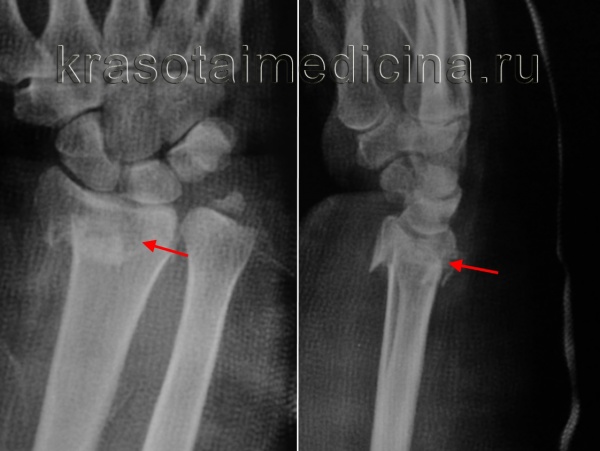

Рентгенография лучезапястного сустава. Перелом дистального метаэпифиза лучевой кости со смещением отломков.

При переломах лучевой кости без смещения накладывают гипс, при смещении после выполнения блокады проводят закрытую репозицию с последующим наложением простой или пластиковой гипсовой повязки. При необходимости для лучшего удержания отломков используют чрезкожную фиксацию спицами. Затем больного направляют на контрольную рентгенографию. При удовлетворительном стоянии отломков гипс сохраняют 4-5 нед. При неудаче репозиции осуществляют попытку повторного вправления. Если фрагменты не удалось сопоставить, показана операция.

Встречаются сгибательные и разгибательные переломы лучевой кости в типичном месте. Чаще возникают разгибательные переломы лучевой кости в типичном месте, характеризующиеся смещением дистального (расположенного дальше от туловища) фрагмента в лучевую сторону и к тылу и некоторым его разворотом кнаружи. Проксимальный (расположенный ближе к туловищу) фрагмент смещается в локтевую и ладонную сторону. При сгибательном переломе лучевой кости в типичном месте периферический фрагмент смещается в сторону ладони и немного разворачивается кнутри, а центральный – смещается к тылу и немного разворачивается кнаружи.